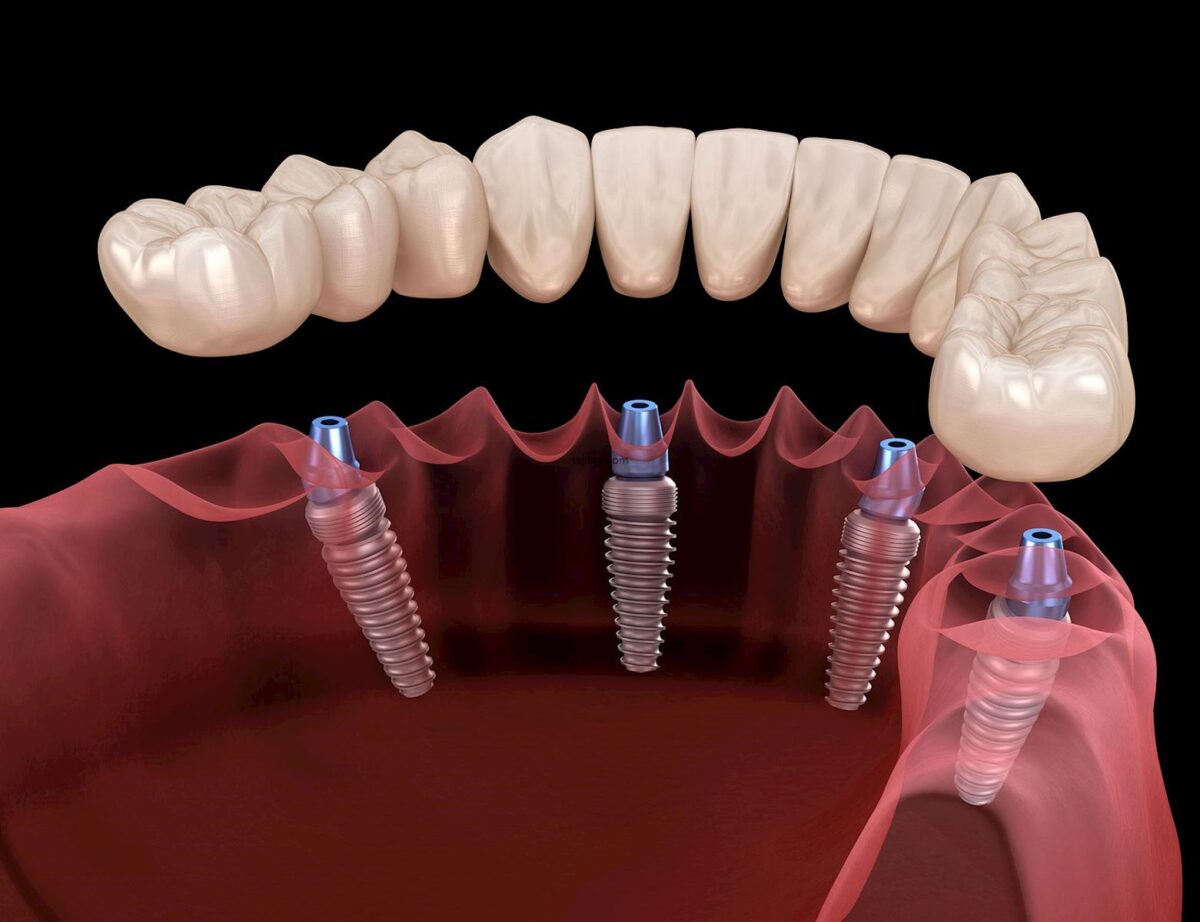

هذه الزرعات طفرة في طب الأسنان الحديث، وهي عبارة عن جذور اصطناعية مصنوعة بدقة في المختبرات السويسرية ليتم غرسها في عظم الفك كبديل دائم للأسنان المفقودة، تعتمد فكرتها على تقنية الالتحام العظمي التي تسمح للزرعة بالاندماج مع أنسجة الجسم الطبيعية لتصبح جزءا لا يتجزأ من الفك، وما يميزها في عيادات عناية هو جودتها الأصلية التي تضمن عدم تآكلها أو تغير لون اللثة المحيطة بها، حيث تخضع لرقابة صارمة تضمن خلوها من الشوائب، مما يوفر للمريض أساسا قويا ومتيناً لتركيب التيجان والجسور السنية بمظهر طبيعي وجذاب تماماً يدوم لسنوات طويلة.

الزرعات السويسرية المرجع العالمي الأول للجودة بفضل الأبحاث السريرية المطولة التي جعلتها تحقق أعلى نسب نجاح في العالم، وفي عيادات عناية نختار لك الأفضل دائما لضمان راحتك، وتعتمد هذه الزرعات على تقنيات معالجة الأسطح المبتكرة التي تسرع من عملية الاندماج العظمي حتى في الحالات التي تعاني من نقص في كثافة العظام، مما يقلل فترة الانتظار بين الزراعة والتركيب النهائي بشكل ملحوظ، الاختيار الصحيح للزرعة المناسبة يتم بدقة بعد دراسة حالة المريض وتصوير الفك بالأشعة ثلاثية الأبعاد لتحديد العمق والزاوية المثالية للغرس، والحصول على النوع الأصلي يضمن لك تفادي المضاعفات الشائعة مثل الالتهابات أو رفض الجسم للزرعة، حيث توفر الصناعة السويسرية متانة استثنائية وقدرة عالية على تحمل ضغوط المضغ اليومية القوية.

- زرعات سترومان العالمية التي تعد الرائدة عالميا في سرعة الالتئام العظمي بفضل سطحها النشط حيويا.

- زرعات نوبل بيوكير المتميزة بقدرتها العالية على التعامل مع حالات الفك المعقدة ونقص كثافة العظام الشديد.

- الزرعات المخصصة للتحميل الفوري التي تتيح للمريض تركيب الأسنان المؤقتة في نفس يوم الجراحة لبعض الحالات.